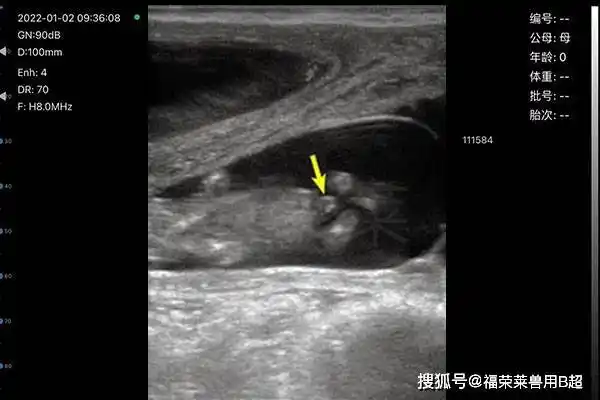

无线牛用b超在母牛繁育过程中的应用_子宫_胎儿_黄体